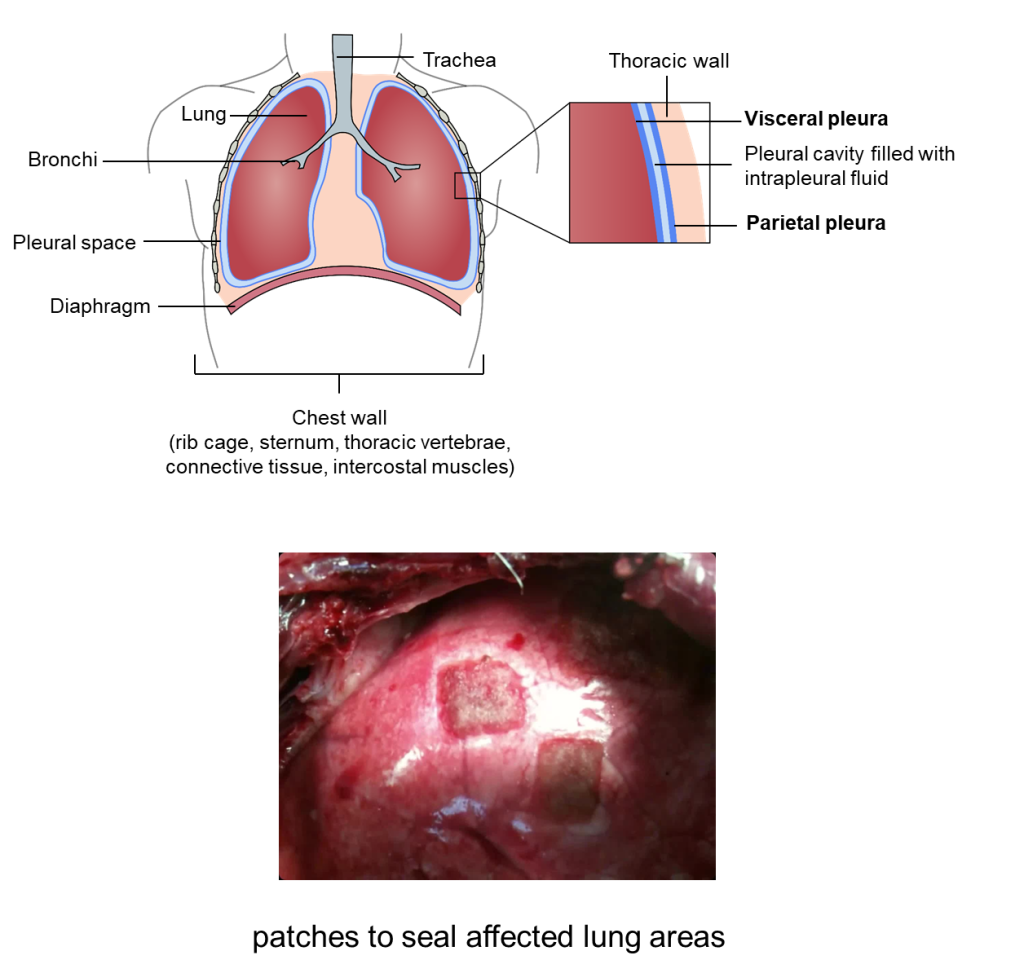

El proyecto Pleuralink comenzará en septiembre de 2025, financiado por el Ministerio de Ciencia, Innovación y Universidades. Buscar mejorar la tecnología y biomateriales actuales que se emplean en cirugía torácica para el sellado de pulmones en una intervención médica y se espera que su contribución en este campo sea muy valiosa. El equipo del proyecto está formado por ingenieros, médicos cirujanos y biólogos y ofrece un marco multidisciplinar único para la realización de un doctorado. Los estudiantes de doctorado que colaboren en el proyecto podrán realizar una variedad de actividades: análisis biomecánicos, diseño de materiales, experimentos mecánicos, experimentos in vitro, análisis microestructurales, estudios histológicos, etc. Buscamos titulados en alguna de las siguientes ramas: ciencia e ingeniería de materiales, ingeniería mecánica y afines, ingeniería biomédica, otras ramas cientifico-técnicas. Si quieres colaborar en el proyecto, realizando tus estudios de doctorado, contáctanos.